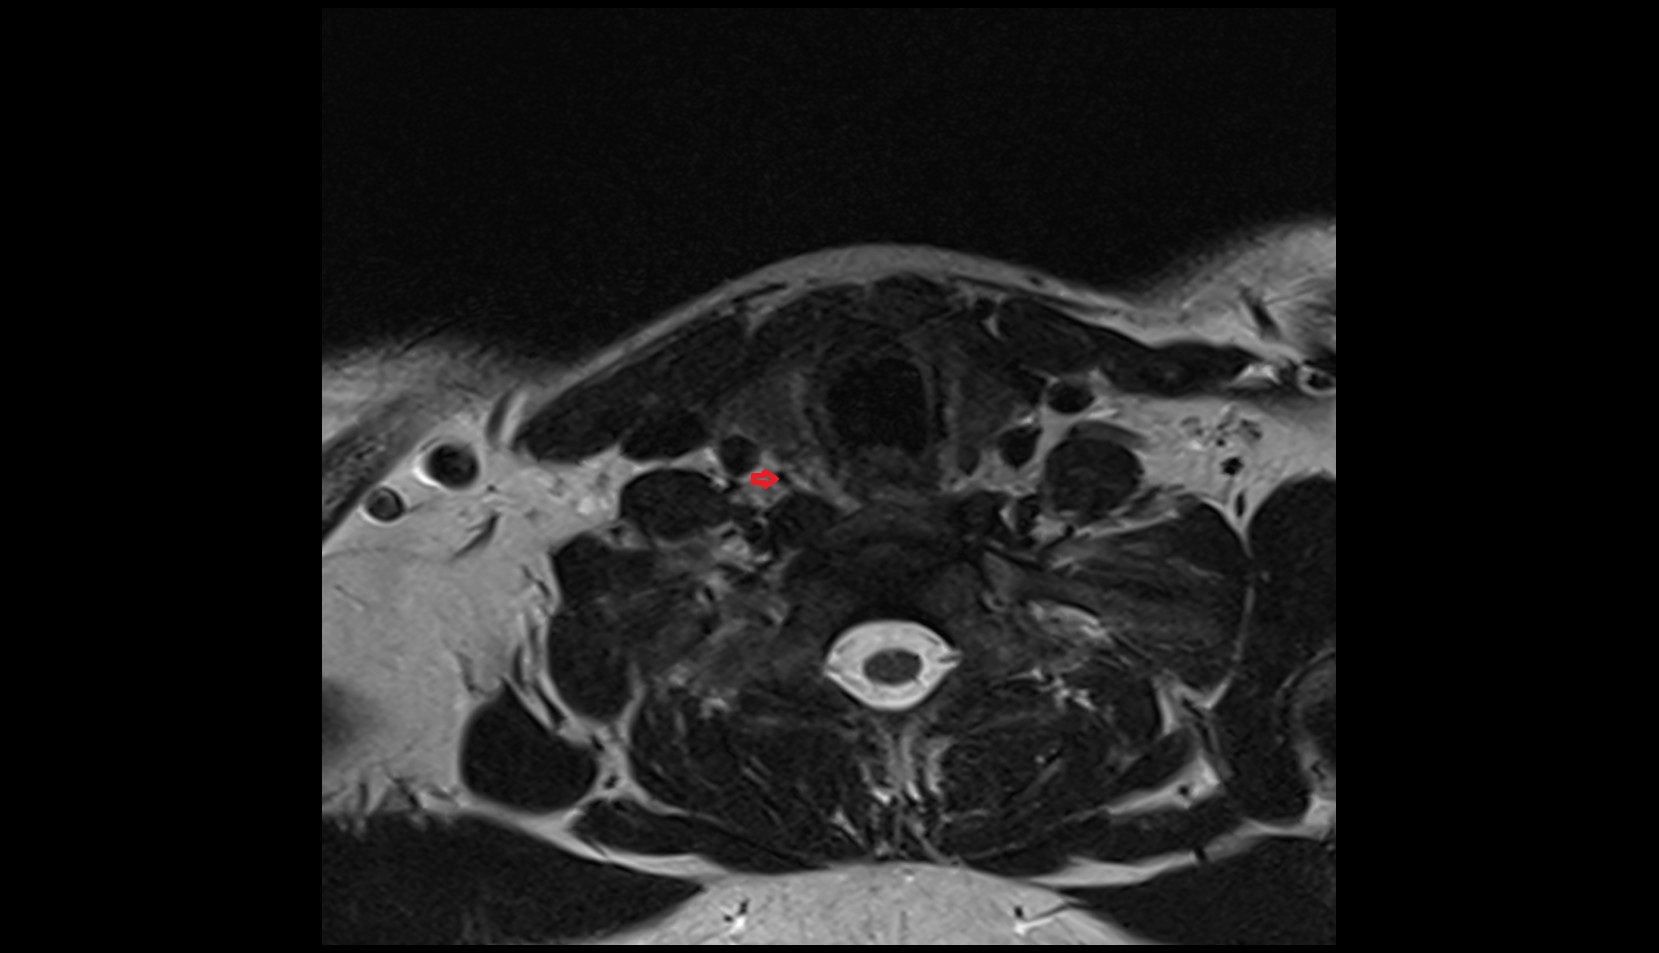

- Peripheral zone of prostate

- Anterior Fibromuscular Stroma of prostate

- Central zone of prostate

- Transitional zone of prostate